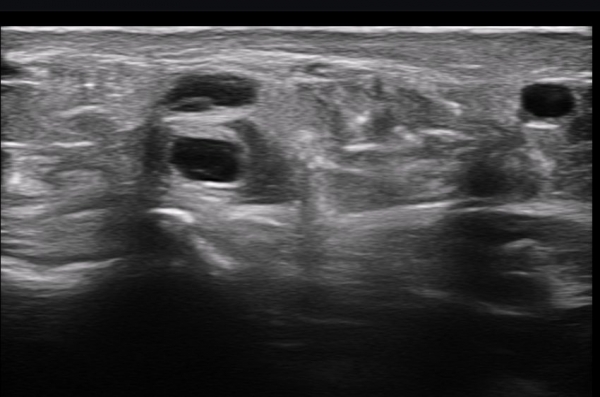

ÃÊÀ½ÆÄ ¼Ò°ß : ºñº¹½Å°æ Ⱦ´Ü¸é°Ë»ç¿¡¼­(»çÁø 1~13) ºñº¹½Å°æÀÇ Àú¿¡ÄÚ ºÎÁ¾°ú ´Üºñ°ñ°Ç³» ³¶Á¾¼º º´º¯ÀÌ °üÂûµÈ´Ù.

ºñº¹½Å°æ Á¾´Ü¸é°Ë»ç(»çÁø 14, 15)¿¡¼­ ºñº¹½Å°æÀÇ Àü¹ÝÀûÀÎ Àú¿¡ÄÚ ºÎÁ¾°ú ºñº¹½Å°æ ½ÉÃþÀ¸·Î ´Üºñ°ñ°Ç³»

³¶Á¾¼º º¯º¯ÀÌ °üÂûµÈ´Ù.